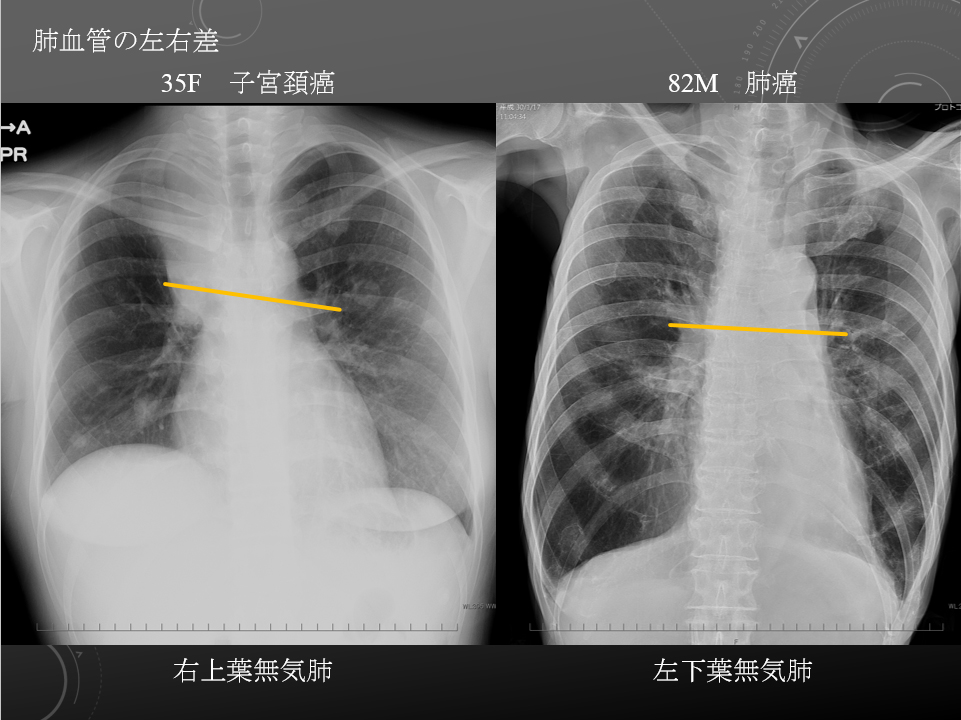

35F 子宮頚癌 多発肺転移 多発リンパ節転移 右上葉無気肺

4ヶ月ほど前から食思不振 体重減少 不正性器出血 咳嗽あり Golden S sign

82M COPD 肺炎 酸素化悪化

原発性肺がん 多発リンパ節転移 左下葉完全無気肺 誤嚥性肺炎